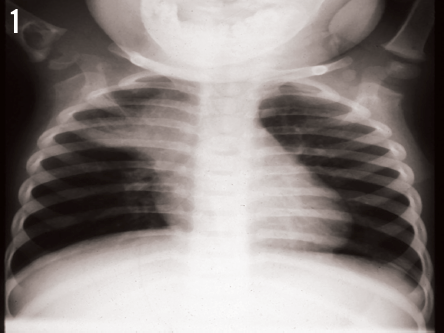

Radiographs of the right shoulder demonstrated a large cystic lesion in the proximal humerus with a lytic process extending across the physis into the epiphysis proximally. A large paratracheal lymph node also was noted on radiographs of both the chest (Figure 1) and the shoulder (Figure 2).

How do you interpret these images?